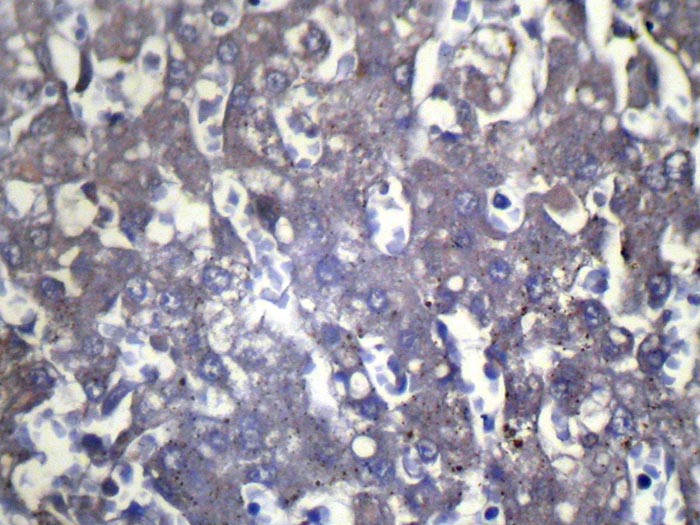

Immunohistochemical analysis of paraffin-embedded Human Liver cancer tissue using #42858 at dilution 1/100.